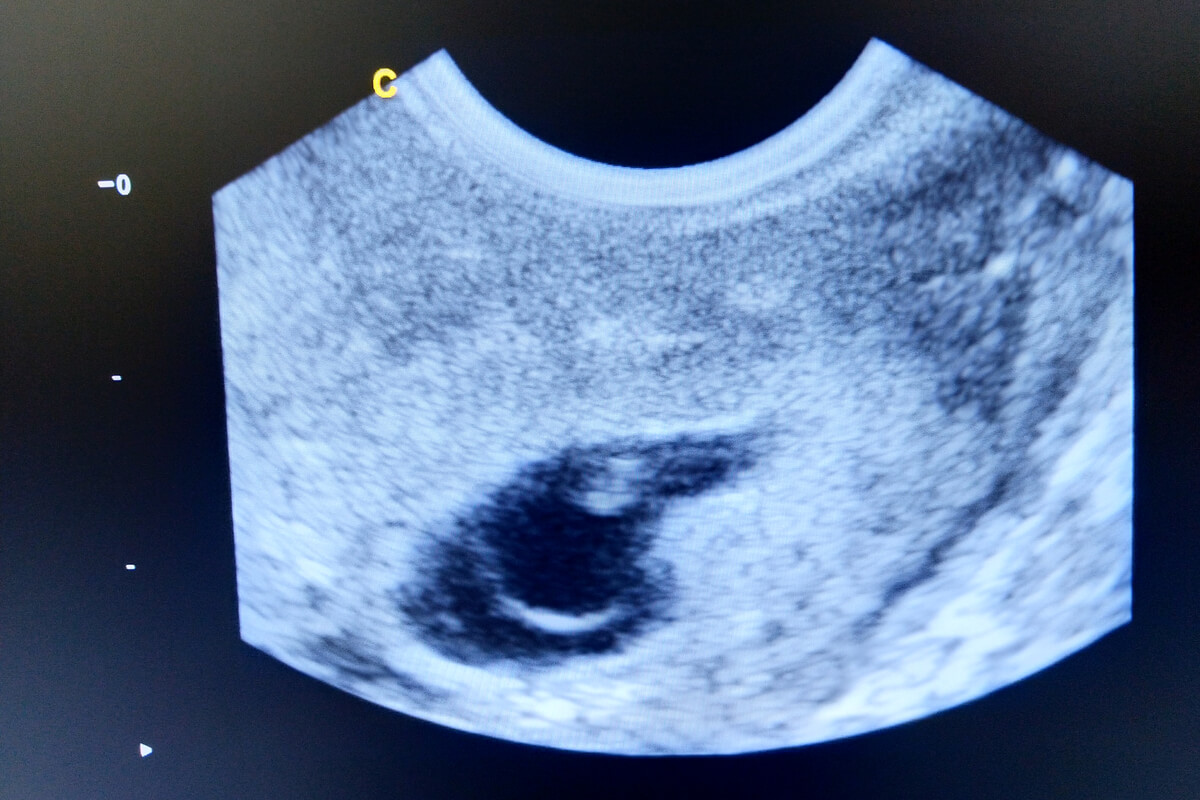

L’échographie est une technique basée sur l’émission et la capture ultérieure d’ondes sonores à haute fréquence. Pour ce faire, le médecin place un appareil appelé transducteur sur le corps de la patiente, toujours à l’aide d’une fine couche de gel qui facilite la technique.

Ledit transducteur émet des ondes sonores -inaudibles pour l’être humain- qui entrent ensuite en collision avec la surface d’organes solides. A ce moment, l’onde est renvoyée vers le transducteur. Grâce à un ordinateur intégré, une image bidimensionnelle ou tridimensionnelle est créée et le médecin l’interprète.

Cette méthode d’imagerie diagnostique est très courante dans les centres de santé. L’échographie transvaginale n’est rien de plus qu’une modalité spécifique dans laquelle on obtient des images plus claires du système reproducteur féminin, contrairement à l’échographie abdominale typique.